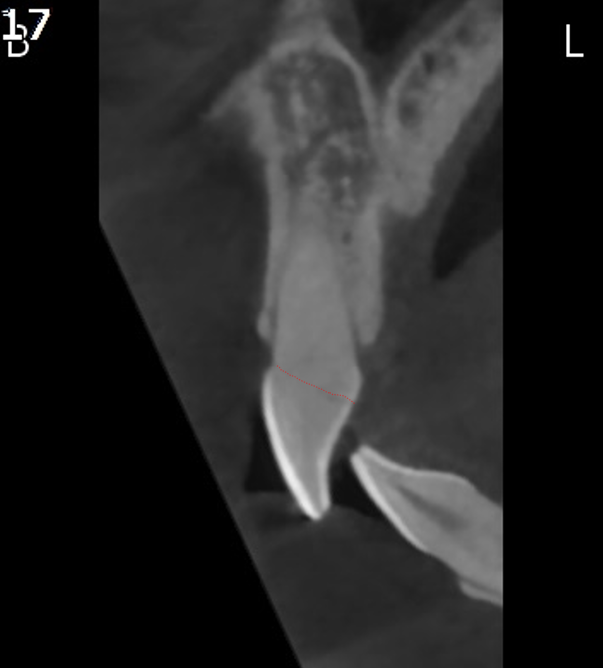

CT 검사 결과 치아의 머리 부분이 전부 부러져서 어쩔 수 없이 발치가 필요한 상황이었습니다.